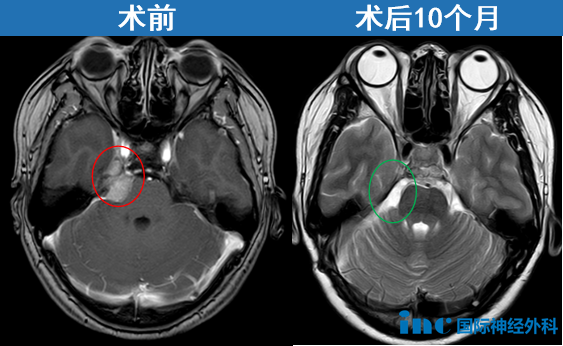

“我不说,没人知道我脑子开了刀”,和许多经由INC巴教授国内成功手术患者类似的是,开颅术后10个月,状态好到很难想象她开过颅。巴教授也为她高兴:"肿瘤完全切除,无任何并发症。在临床恢复方面,我非常高兴看到患者目前神经功能状态良好,尤其面神经及第六脑神经功能完全保留。衷心祝愿她一切顺利。建议于2026年夏季进行下一次 MRI 复查,届时我可以再次评估其影像学表现。"

对于很多患者来说,体检发现脑瘤往往如同晴天霹雳。但事实上,早期发现、尽早治疗恰恰是最大的幸运。就像周女士的案例,这个“安静”的脑膜瘤,术中竟发现已经与周围的神经血管形成了紧密粘连,这个“变数”让手术难度大大增加。

现代影像学技术(比如CT或MRI)虽能发现肿瘤,却难以完全呈现这些细微的粘连关系。只有在手术显微镜下,才能看清这些错综复杂的“生命线”。值得庆幸的是,由于发现及时,即便肿瘤已经形成粘连,仍在国际神外大咖巴教授可成功手术的范围内。